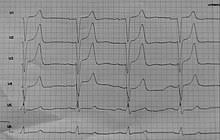

Ein ungewöhnlich hoher Kaliumwert oder ein unregelmäßiger Herzschlag machen stets eine Notfallbehandlung notwendig. Nierenerkrankungen Medikamente welche die Nierenfunktion beeinträchtigen und der Konsum von zu viel Kalium-Ergänzungsmitteln. Im Gegensatz dazu spricht man ab einem Serumkalium von mehr als 52 mmoll Erwachsene von einem Kaliumüberschuss Hyperkaliämie.